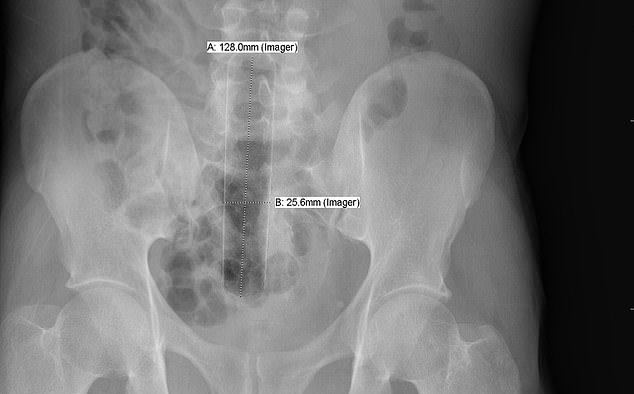

It was found that the rectum is the most common place for bizarre items to get stuck. Some of the objects include household items such as aerosol can, plastic pill bottle, beer bottle, and a plastic cigar holder.

Other articles such as a ‘leg of a telescope’, ‘cell phone’ and ‘Christmas ornament ball’ have also been found in some patients.